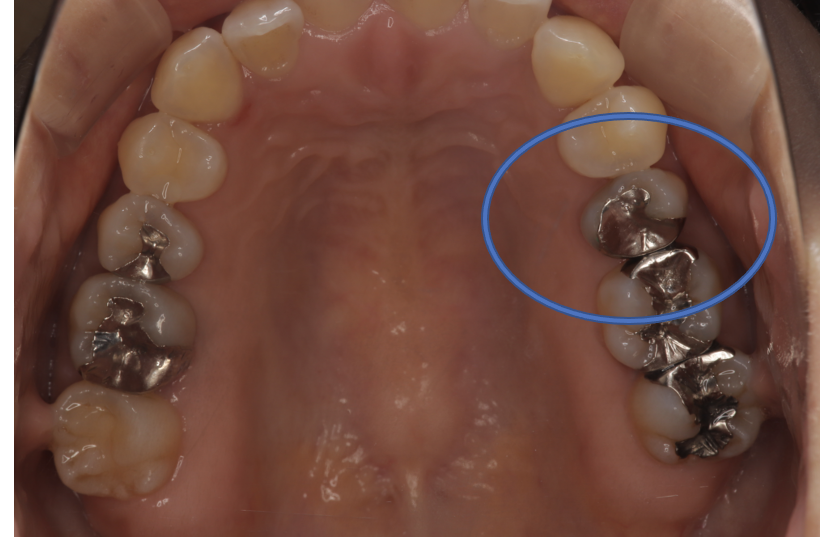

フルジルコニアCr 9 No.31

Before

| 治療方法 | フルジルコニアCr 虫歯などで失った歯質を天然歯と同じ色・質感のセラミックの一種であるジルコニア(人工ダイヤモンド)で補う治療法。 |

| 治療のデメリット | 変色がなく耐久性の高い治療ですが、歯周病や二次虫歯を予防するためには歯科医院での定期的なメインテナンスが大切です。 |

| 費用 | ¥89,000 |

| 通院回数 | 1ヶ月〜6ヶ月 |

| 備考 | 院長より 銀歯の内部に虫歯が進行してしまっていたケースです。中を開けて見てみると、外から想像するよりもはるかに虫歯が広がってしまっていました。幸運にも神経を保存できたので、生きた臓器としてまだ使うことが可能です。残存歯質がかなり薄く弱くなってしまったので、ジルコニアで被せて守ってあげています。反対側の歯は、残念ながら虫歯の進行が神経まで及んでいて、根の治療が必要になってしまったケースです。 |